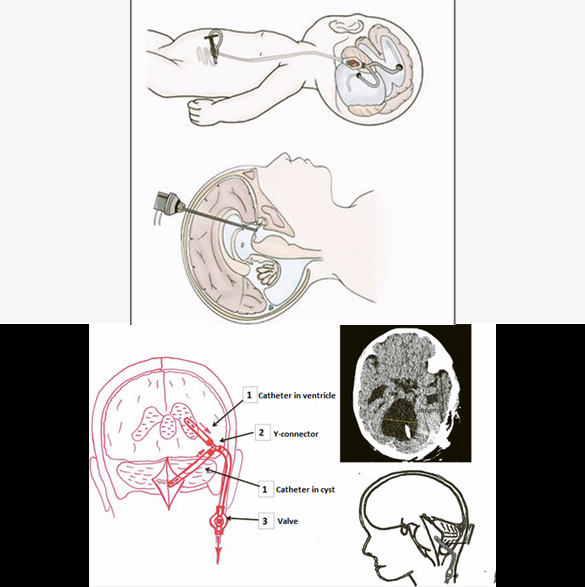

VP Shunt Procedure for Hydrocephalus

Ventriculoperitoneal (VP) shunt is a type of surgical treatment for hydrocephalus. VP shunt is placement of a catheter inside the body that drain the excessive fluid (CSF) from the brain to abdomen where it is absorbed, creating an artificial pathway to control CSF volume. VP shunt placement is one of the common procedures in neurosurgery. VP shunts are generally placed for life with a few exceptions. There are many types of VP shunts available depending on the quality (Medtronic, Integra, etc.) and functionality (fixed pressure, programmable). There are some other shunts than can also be performed for hydrocephalus; Lumboperitoneal (LP shunt), Ventriculoatrial (VA shunt), Ventriculopleural (VPl shunt). A few complications of the shunt surgery may be infection, shunt blockage, and over-drainage.

Endoscopic Third Ventriculostomy for Hydrocephalus

Endoscopic third ventriculostomy (ETV) is another type of surgical treatment for hydrocephalus where a neurosurgeon inserts an endoscope (a thin, lighted tube with a camera) through a small hole in the skull and into the brain's ventricles. It creates a diversion in the pathway of fluid (CSF) in the brain, with the help of an endoscope. ETV can prevent from placing a permanent catheter (VP shunt) in the brain. ETV is generally an elective procedure and can only be performed in some specific cases of hydrocephalus. It is usually avoided in emergency cases but can be performed even in infections. While ETV is a successful procedure for many, the success rate can vary depending on the cause of hydrocephalus and the patient's individual circumstances. Complications of this surgery may include wound infection, intracranial bleeding (failure to complete the procedure), and postoperative increasing hydrocephalus.

Dandy-Walker Malformation Surgery

Dandy-Walker Malformation treatment is focused on managing the associated hydrocephalus and controlling the increasing intracranial pressure to improve the developmental and neurological outcomes. The Dandy-Walker malformation related hydrocephalus is treated with a Ventriculoperitoneal (VP) shunt same as for a usual case of hydrocephalus, with or without the need of shunting the enlarged cyst (Cystoperitoneal shunt) in the posterior part of the brain. Sometimes, cystoperitoneal shunt is the only surgery that patient needs. Endoscopic fenestration may be helpful in a few cases, avoiding any shunt placement. Complications of the surgery are mainly shunt related like infection, blockage, or slippage/migration of shunt.